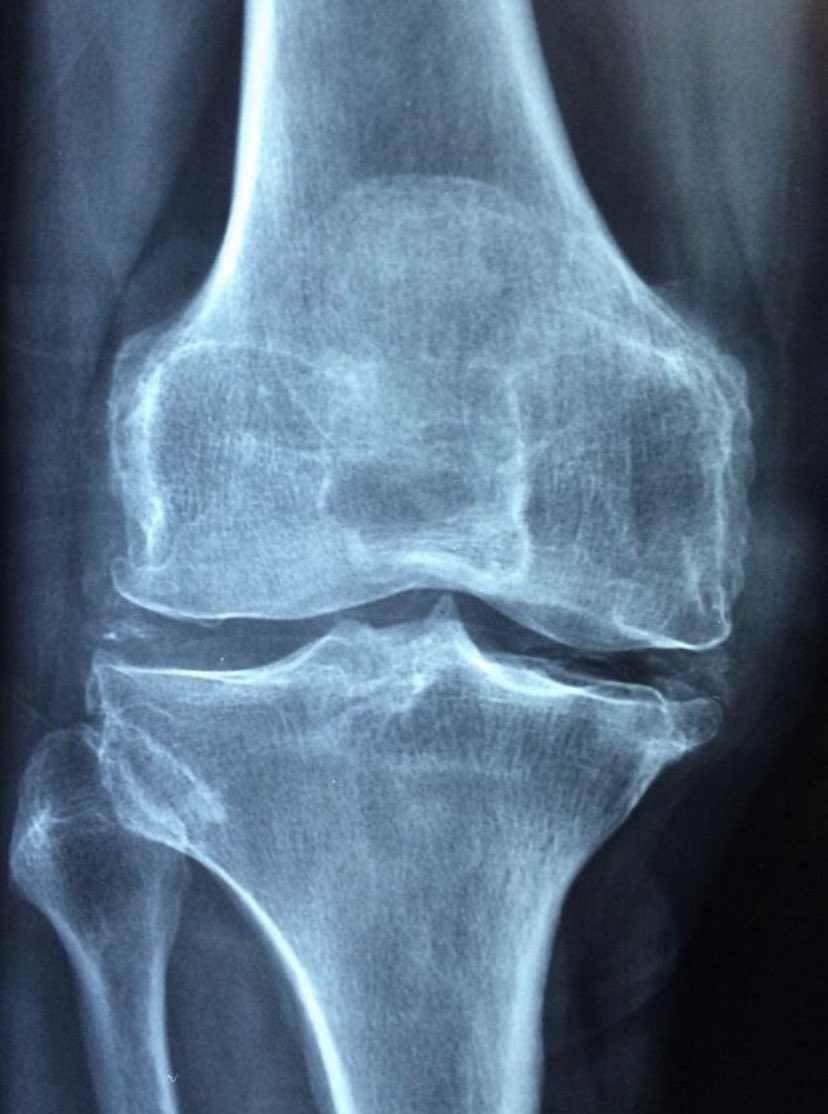

#CBD as a treatment for arthritis and joint pain Results: ⬆️CBD use was associated with improvements in pain (83%), ⬆️physical function (66%), ⬆️sleep quality (66%). pubmed.ncbi.nlm.nih.gov/35999581/

#CBD led to improvements in pain (83%), physical function (66%), and sleep quality (66%) -- especially people suffering from #osteoarthritis (I would rather give someone CBD than NSAIDS which destroy kidney..) lnkd.in/evA64xEW

CBD as a treatment for arthritis: CBD use was associated with improvements in patient's arthritis symptoms and reductions in other medications. Reduction in pain (83%), physical function (66%), and sleep quality (66%). pubmed.ncbi.nlm.nih.gov/35999581/

CBD may be effective in the treatment of joint pain according to a survey. "In a survey by the Core Institute/Banner University Medical Center in Phoenix, USA, with 428 patients suffering from arthritis the use of CBD was associated with improved pain..” lnkd.in/gxNes5x8